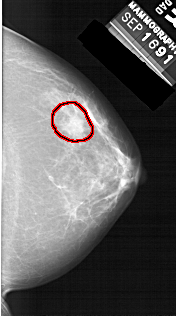

FILE: A_1456_1.RIGHT_CC.OVERLAY

TOTAL_ABNORMALITIES 1

ABNORMALITY 1

LESION_TYPE MASS SHAPE IRREGULAR MARGINS ILL_DEFINED

ASSESSMENT 4

SUBTLETY 2

PATHOLOGY BENIGN

TOTAL_OUTLINES 1

BOUNDARY